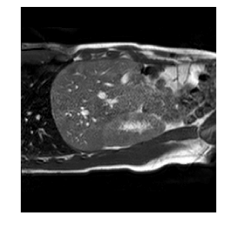

With this motivation, [6] proposed a convolutional neural network (CNN) based approach for temporal interpolation of navigators. Their CNN takes as inputs a fixed number of acquired images and learns to predict the missing images directly in the intensity space. This approach, which we call the Simple Convolutional Interpolation Network (SCIN), is a ’black-box’ formulation that does not incorporate any prior information about the interpolation process. Image prediction is guided only by the cost function used to optimize the network parameters. The issue with this is that it is unclear whether the image similarity measures that are generally used as cost functions suffice to ensure fidelity of the generated images to the original images. Indeed, Fig. 1b shows a case where an image interpolated using SCIN is quite blurry and misses several liver and lung structures present in the original image.

(a)                                (b)                                (c)

Figure 1: (a) Ground truth and (b,c) interpolated images from (b) baseline (SCIN) and (c) proposed method (MFIN). The image interpolated via SCIN is heavily blurred and misses several lung and liver structures, while the proposed method is able to preserve the details in the ground truth image.